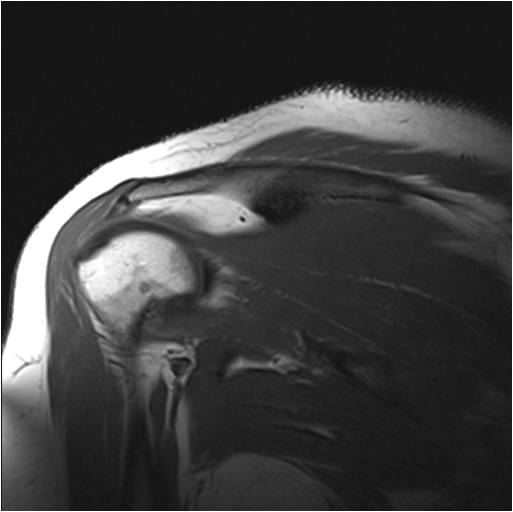

Radiograph #1

Glenohumeral Joint and Quadrangular Space

Identify: Teres minor, long head triceps, surgical neck humerus, teres major. Axillary nerve, head humerus, glenoid fossa, deltoid, supraspinatus, acromion.